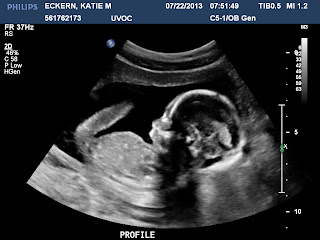

I was trying to wait as long as I could to go back to the hospital because I didn't want us to get sent home again. Around 8PM I was in more pain than the night before and decided we better go to the hospital, even if it was just to get some medicine again so I could sleep. My contractions were hurting so bad and I was so worried that they'd say I was still at a one and then we would just repeat what had happened the night before:/ But this time the nurse told me I was dilated at a four! Halle-freakin-lujah! Haha, I was pretty dang excited to know that Henry was on his way! They gave me an epidural (again, Hallelujah!) and I fell asleep for a few hours. I woke up a while later and they said we needed to wait a little bit longer and then I could start to push. Around 3AM they started me pushing and at 3:56 little Henry Scott Eckern was born, 7 lbs 7 oz and 19.5 inches long with a whole lot of hair! :) He was so perfect and everyone agreed that, other than his cone head, he was definitely the cutest baby they'd ever seen:)